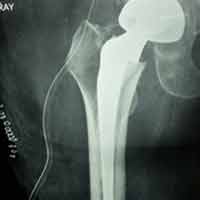

Case:7 Fracture Neck Femur with Implant failure and Re-Fixation with hemi-arthroplasty

Alcoholic Gardener by profession had slipped in bathroom & fell. He sustained fracture neck femur.He was operated with closed reduction & CC Screw fixation under IITV. Two weeks’ post fixation he again fell & sustained fracture in sub trochanteric region. He was treated with Hem-Arthroplasty with Tension band wiring.

Pre-Op

Post-Op

Post Fall

Oblique-Post Fall

Lat-Post Fall

Lateral-Post Prosthesis Fall

Post Prosthesis Fall

Post Uninon-3Months